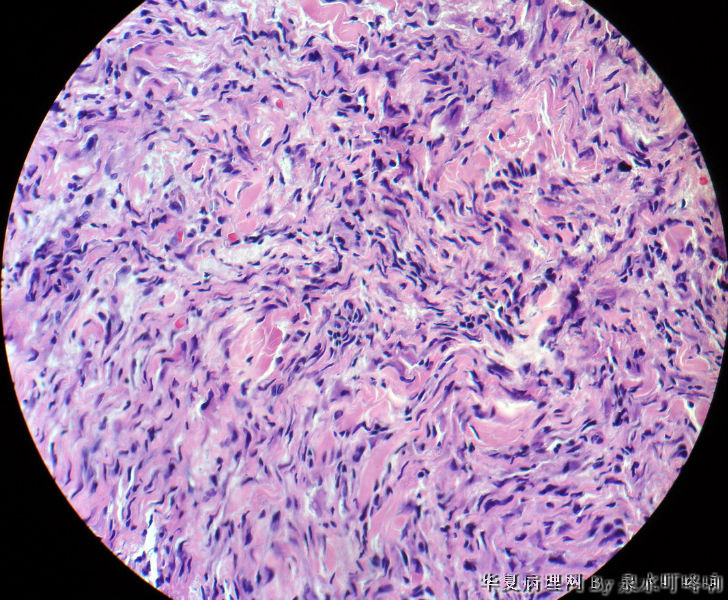

女,39岁,颈后部肿物半年。

大体:灰白皮表肿物一个,呈半球形,直径0.9厘米,高出皮表0.9厘米,切面灰白,质中。

北京肿瘤医院会诊:纤维组织细胞瘤。